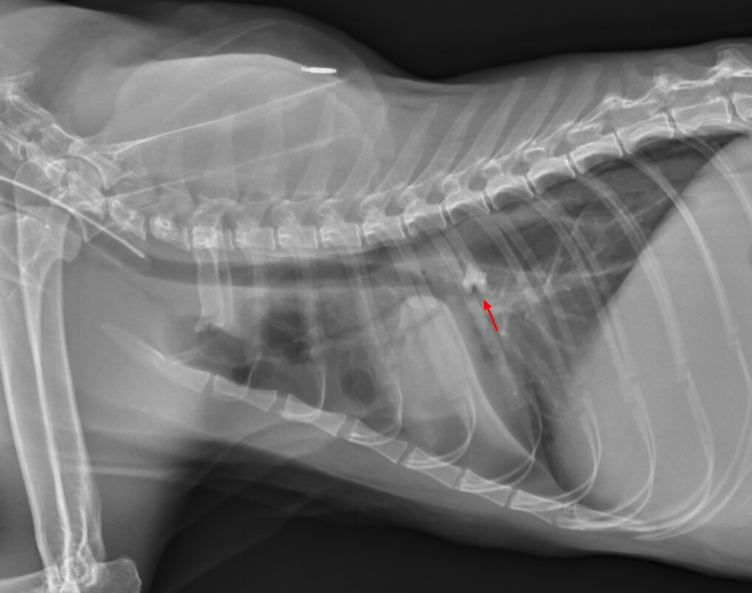

고양이가 가 농흉이 생겼는데 그 원인이 빠진 이빨을 숨 쉬다가 폐로 넘어가서 생겼다,라는 세상에 이런 일이 같은 논문이다.

드문 경우에 해당하니 너무 겁먹을 것은 없지만, 농흉이 생겼을 때 혹, 이물에 의한 농흉인지를 확인해야 한다는 경각심을 우리에게 제시한다고 하겠다.

농흉뿐 아니라 기흉도 있는 걸 볼 때 이빨이 폐를 뚫기는 뚫었나 보다 싶긴 하다. 아니면 농흉 천자하다가 폐를 찔렀거나.